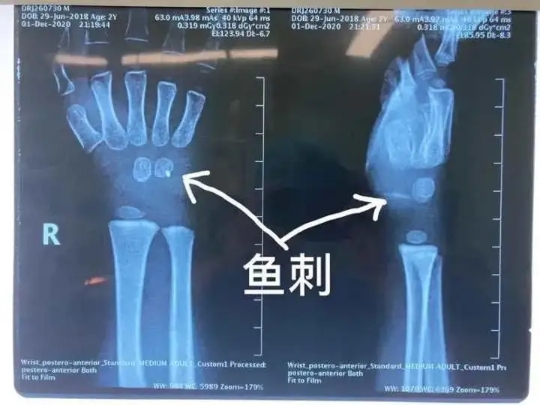

近日,杭州市兒童醫(yī)院骨科還接診了一名被魚刺扎傷手腕的小患者

原來,調(diào)皮的元元(化名)在家拿著魚玩耍,結(jié)果不小心忽然摔倒,魚刺深深地扎進(jìn)了他的手腕。

醫(yī)生拍片檢查后發(fā)現(xiàn),魚刺已經(jīng)深及元元的手腕內(nèi)部約一厘米左右的位置。雖然體表傷口細(xì)小,但是內(nèi)部傷口附近神經(jīng)、血管交織錯雜,如不及時取出魚刺,會嚴(yán)重影響孩子的手腕功能。

手術(shù)室里,骨科醫(yī)生小心翼翼地取出魚刺后,再次探查周圍神經(jīng)、血管、肌腱,確定沒有殘留及其他損傷后,縫合傷口。經(jīng)過兩個多小時,終于為孩子解決這惱人的“不速之客”。